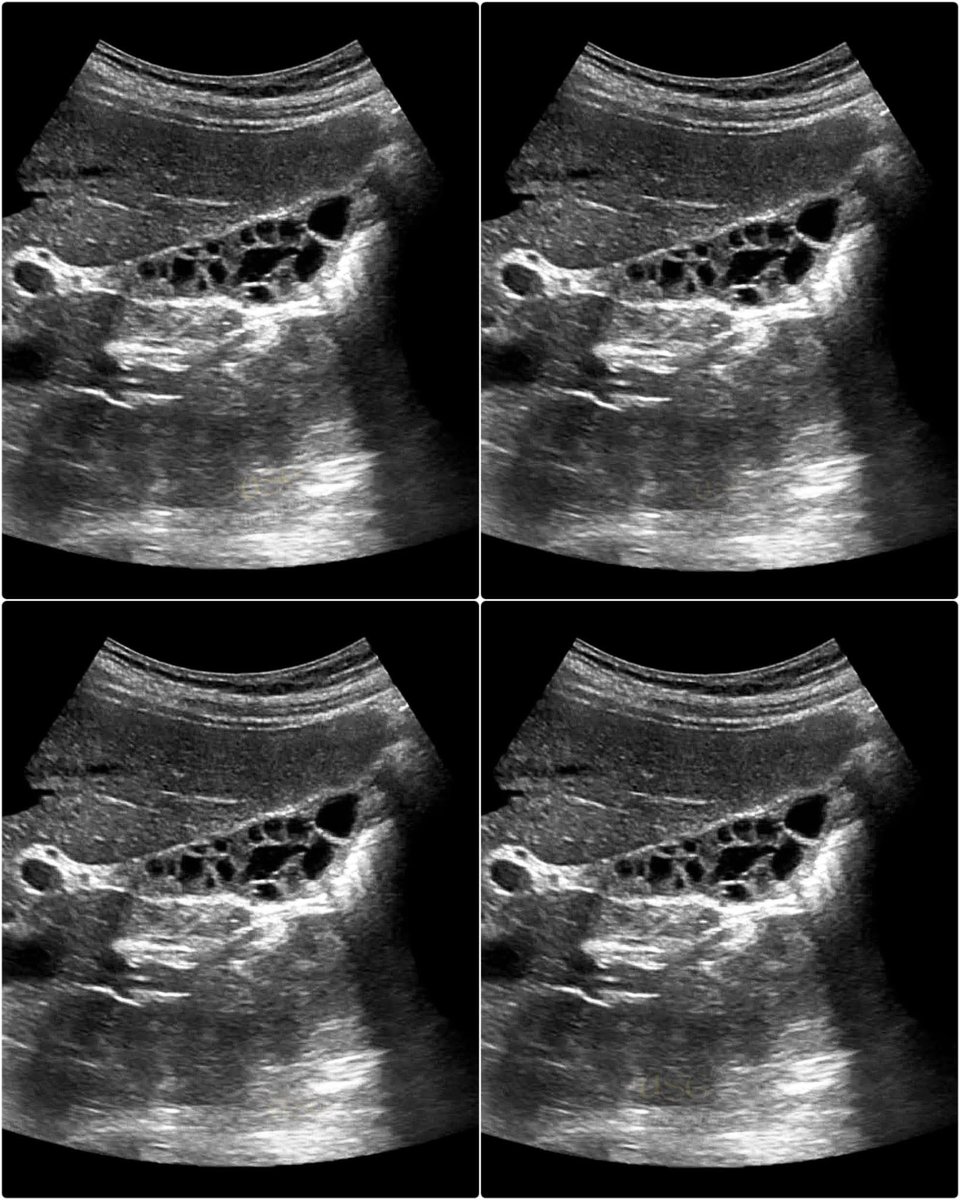

honeycomb gallbladder appears as a multiseptated gallbladder with a thickened wall and multiple non-shadowing echogenic septa (internal walls) crisscrossing the lumen. #EchoTech

1